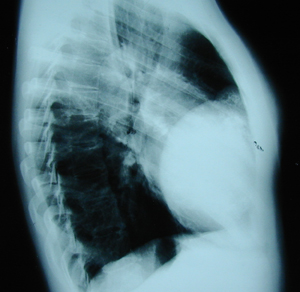

Περίπτωση Νο 2

Εικόνα 4

Οπισθιοπροσθία ακτινογραφία του θώρακος μετά από την αφαίρεση του όγκου (χονδροσάρκωμα). Η αποκατάσταση του θωρακικού τοιχώματος έγινε με την τοποθέτηση μοσχεύματος από ακρυλική ρητίνη (Methyl-Methacrylate-cement), τσιμέντο και πλέγμα Marlex Mesh (τεχνική σάντουιτς). Διακρίνονται και τα συρμάτινα ράμματα που χρησιμοποιήθηκαν για την καθήλωση του

μοσχεύματος.